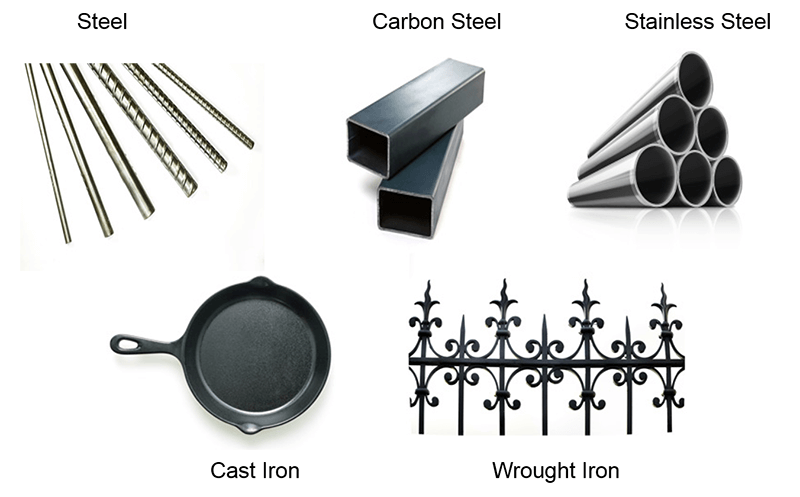

The most important consideration is ferrous metals. These metals pose the greatest risk to everyone in the MRI suite because of their strong attraction to magnets. Products created of steel or steel products are of greatest concern. Steel is derived from iron ore. Iron ore is used as additives and alloys with many other types of metals.

At times, these types of metals are used to save money or provide additional strength to other types of metal. For this reason, ALL metal should be tested with a FERROUS METAL DETECTOR, not just a metal detector. A metal detector tells us it is metal, a ferrous metal detector tells us if it’s ferrous.

Ferrous: